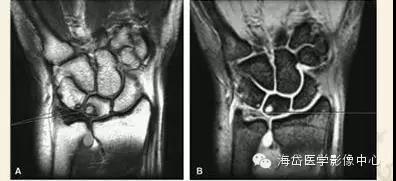

①X线:尺骨阳性变异(尺骨远端伸长)或处于中立位;月骨、三角骨坏死呈低密度小囊状改变以及月骨、三角骨关节面下软骨硬化,病变部位位于月骨尺侧近端和三角骨的腰部;尺骨小头相对关节面下软骨硬化或小囊性变。

②MRI:MRI对骨髓变化敏感,在骨损伤早期就能反映出骨髓水肿性改变,可做到早期诊断。

随压迫时间延长MRI可见高信号(T2WI)逐渐增强,并形成透镜样改变,晚期形成“双线”或“双环”征。“双环”征提示坏死区内可能有新骨形成,“双线”征表明骨坏死区有瘢痕组织形成。

由于尺骨阴性、阳性变异引起的骨坏死是可逆的,当尺骨变异被纠正后骨坏死可以转化为正常骨结构。因此MRI除可用于早期诊断外还可作为有效的动态观察手段,当骨髓水肿性变化无减轻、消失,反而逐渐明显时,提示临床应早期解除桥联状态(主要是解除压迫),可有效防止月骨、三角骨坏死的发生或降低其发生率。